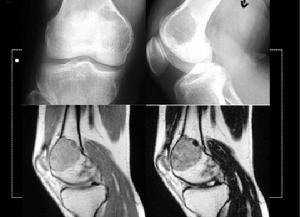

軟骨黏液樣纖維瘤位於長骨的腫瘤多累及乾骺端,呈偏心生長的卵圓形或圓形溶骨病變,向外生長、膨出、邊緣清晰、硬化,也可出現局灶性邊緣不肖。如繼續生長,骨殼淺缺,但無新生骨形成。腫瘤大小直徑為1-10cm,平均3cm。病變外緣皮質骨變薄膨脹,無骨膜再生,邊緣骨皮質消失、破壞,可竇及軟組織內。突破邊緣骨皮質被掀起呈盤狀,出現小的Codman三角。在X線上腫瘤鈣化少見,但組織學觀察1/4可發現鈣化灶。病理骨折少見。